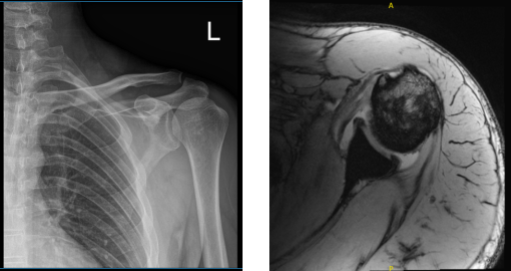

X-ray results showed no significant degenerative changes that’s why we decided to take an MRI. MRI impression as follows: Plate tear of the intra-articular portion of the long head of the biceps tendon and the large stump of proximal fibers displaced into the anterior medial joint recess.

The distal fragment is retracted into the upper arm distal to the pectoralis major attachment. There is moderate biceps tenosynovitis. Moderate subscapularis tendinosis with partial-thickness articular sided tearing at the insertion. Mild to moderate supraspinatus tendinosis.

MRI of the biceps